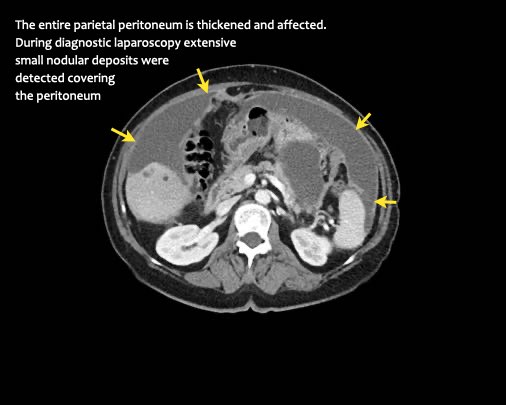

Ca lâm sàng 1

Cuộn qua các lát cắt.

Bạn có thể phát hiện tất cả các tổn thương cấy ghép phúc mạc không?

Bệnh nhân này đã được phẫu thuật và toàn bộ phúc mạc được ghi nhận phủ kín bởi các tổn thương u dạng kê.